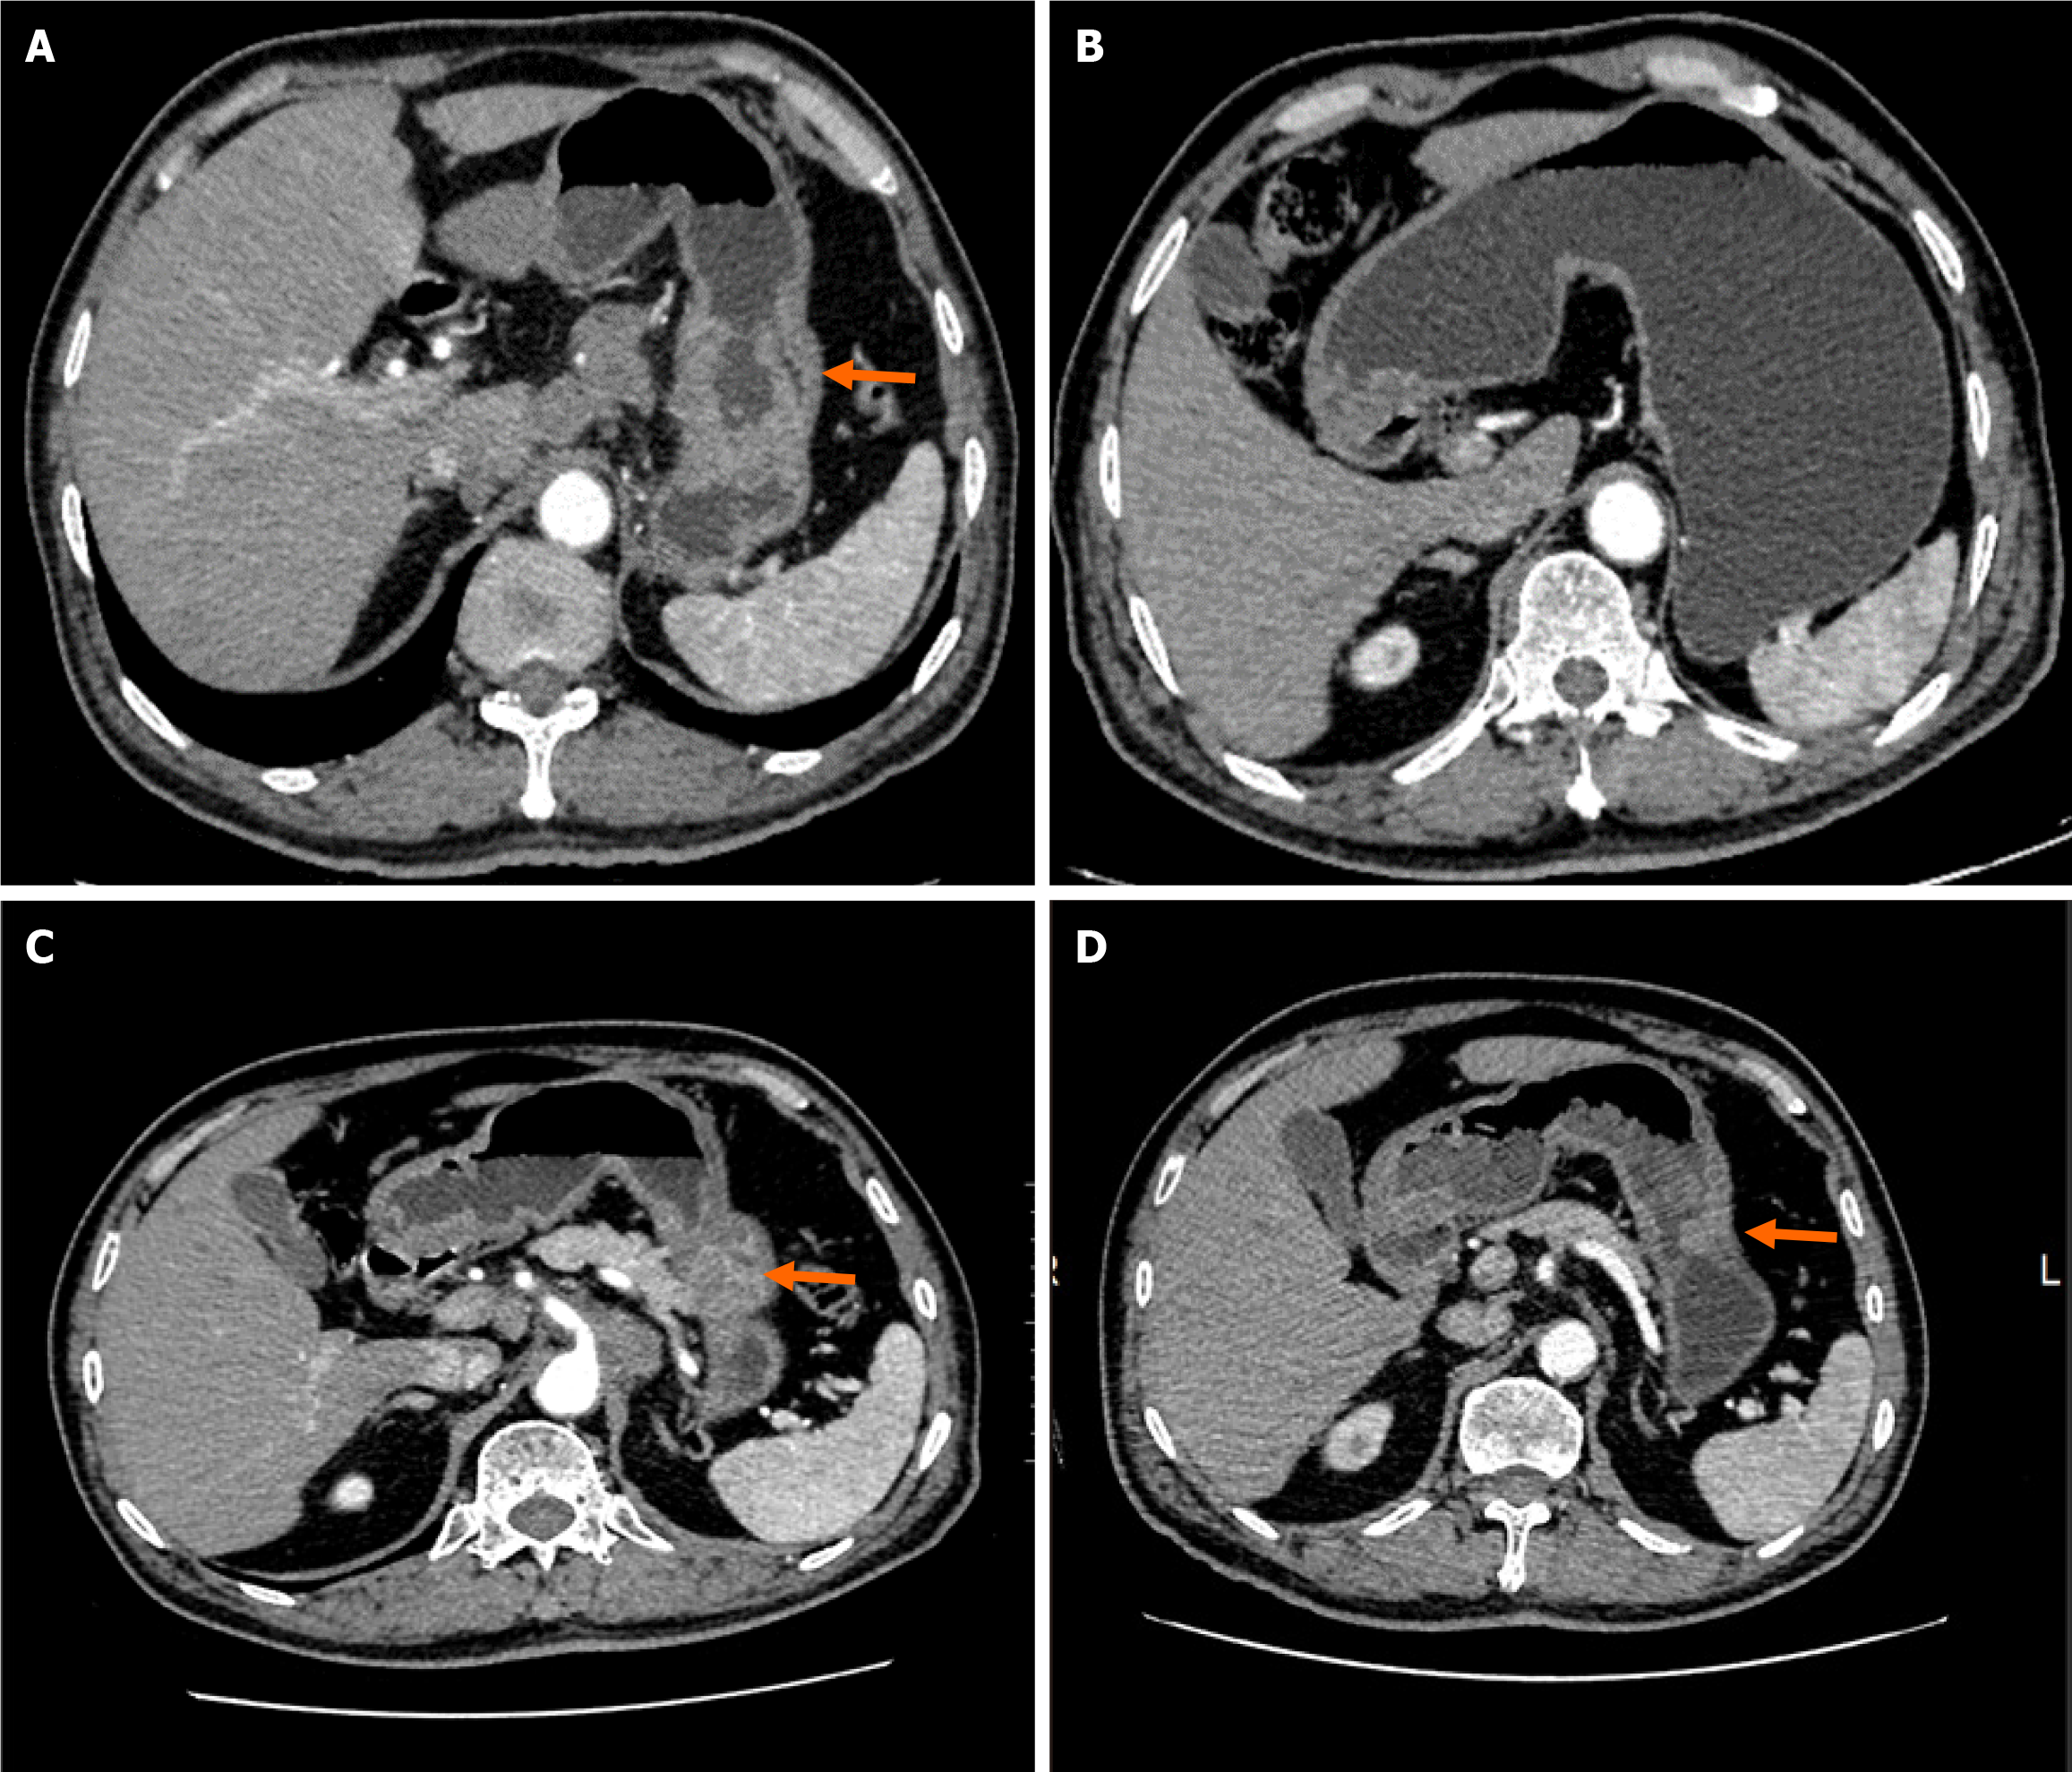

Computed tomography (neck + chest + abdomen; plain scan + enhancement) showed enlarged lymph nodes in the anterior upper mediastinum, occupying space in the greater curvature of the stomach. In addition, multiple intrahepatic metastases with multiple lymph node metastases were observed in the hepatogastric space and around the abdominal aorta (Figure 1). Gastroscopy examination revealed a mass in the gastric body (Figure 2).